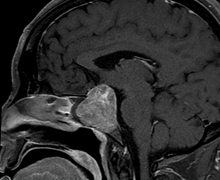

Case 1: 35/ M

- Pre-operative Coronal and Sagittal contrast enhanced T1W images show a well circumscribed homogenously enhancing sellar mass with suprasellar extension (Figure 1).

Figure 1